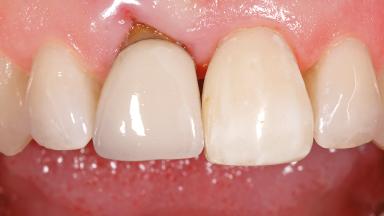

Early Placement of an Implant in a Maxillary Right Central Incisor Site

This 41-year-old female patient was referred to the clinic for the replacement of the right central incisor, since the tooth had developed a root fracture in the long axis that made extraction necessary. The healthy, non-smoking patient was first seen with the tooth still in place. A detailed Esthetic Risk Assessment was performed.The patient was worried about her dental esthetics and had high expectations for a successful treatment outcome from an esthetic point of view. The patient had a medium lip line that displayed parts of the gingiva in the anterior maxilla upon smile.

Lip Line No exposure of papillae Exposure of papillae Full exposure of mucosa margin

Periodontal Phenotype Low-scalloped, thick Medium-scalloped, medium-thick High-scalloped, thin